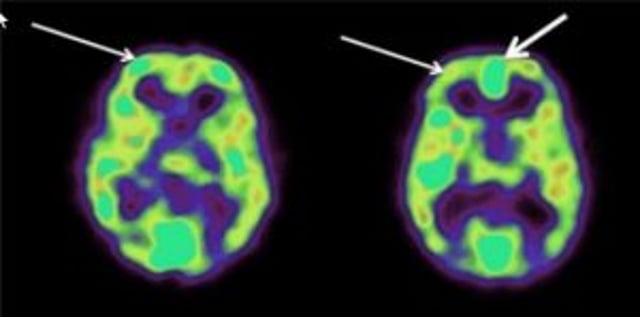

38 Newberg, A. B., Wintering, N. A., Yaden, D. B., Waldman, M. R., Reddin, J., & Alavi, A. (2015). A case series study of the neurophysiological effects of altered states of mind during intense Islamic prayer. Journal of Physiology – Paris, 109, 214-220.

39 Ibid.

43 Newberg, et al.. (2015).